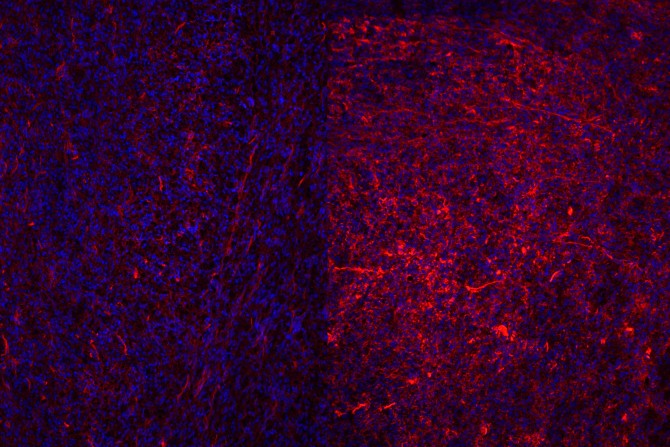

In microscope images of the extracellular matrix and cells, cells are stained in blue and collagen in red. Regressing tumors on the left are surround by less dense collagen compared to resistant ones (right) with dense collagen.

The ECM caught the team's attention because researchers noticed striking changes in collagen, the matrix's main structural protein, during treatment: The ECM becomes unusually dense and overproduced. "What we wanted to know is whether the changes in the ECM were just a side effect of therapy, or if they actually contributed to drug resistance," said Dr. Chia-Hsin Hsu, doctoral student and first author of the study.

"It was thrilling to see how changing the extracellular matrix could completely reshape the immune landscape of a tumor," Hsu said. "Under the microscope, we could literally see cytotoxic T cells spreading more evenly once the ECM was reduced. It felt like uncovering a hidden mechanism that had been holding back the immune system from doing its job."